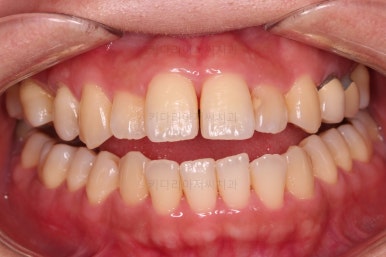

초진 시, 입안의 모습이에요.

결손부위가 눈에 띄고요.

결손부위가 양쪽에 있다보니 윗니 중간에 틈새가 벌어졌네요.

뒤쪽의 빈공간으로 치아들이 도미노처럼 쓰러져서 그렇습니다.

앞니의 약간의 틈새, 약간의 삐뚤어짐, 약간의 중앙선 틀어짐 등 심하진 않으나 약간씩의 문제점들이 있네요.